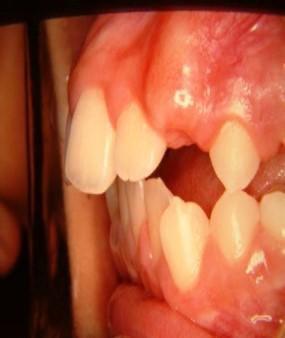

Γ3γ. έκτοπη ανατολή μονίμων δοντιών Συμβαίνει όταν το διάδοχο μόνιμο δόντι ανατέλλει σε άλλη θέση από τον πρόγονό του.

Εδώ παρατηρούμε τον κυνόδοντα να ανατέλλει ανάμεσα στον κεντρικό και πλάγιο τομέα. Η έγκαιρη ορθοδοντική παρέμβαση στην κατάλληλη ηλικία προλαμβάνει μελλοντικές συγκλεισιακές ανωμαλίες.